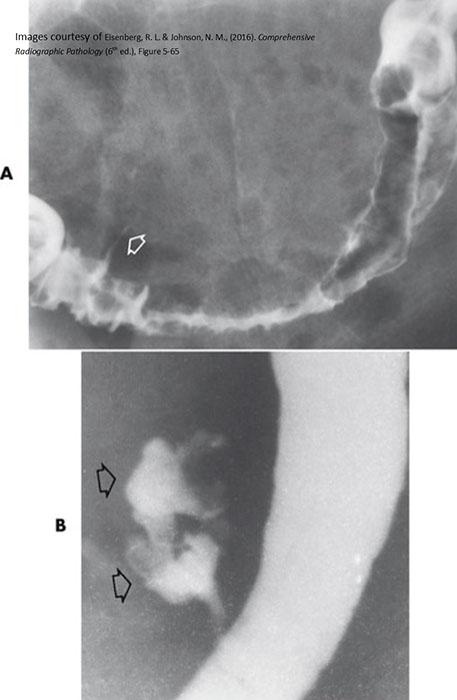

What is intussusception?

Telescoping of a proximal bowel segment into a distal segment, causing obstruction.

Why is intussusception dangerous?

It compresses the mesentery, cutting off blood supply and causing necrosis.

Bowel contents cannot pass through the telescoped segment.

Where does intussusception most commonly occur in children?

At the ileocecal valve.